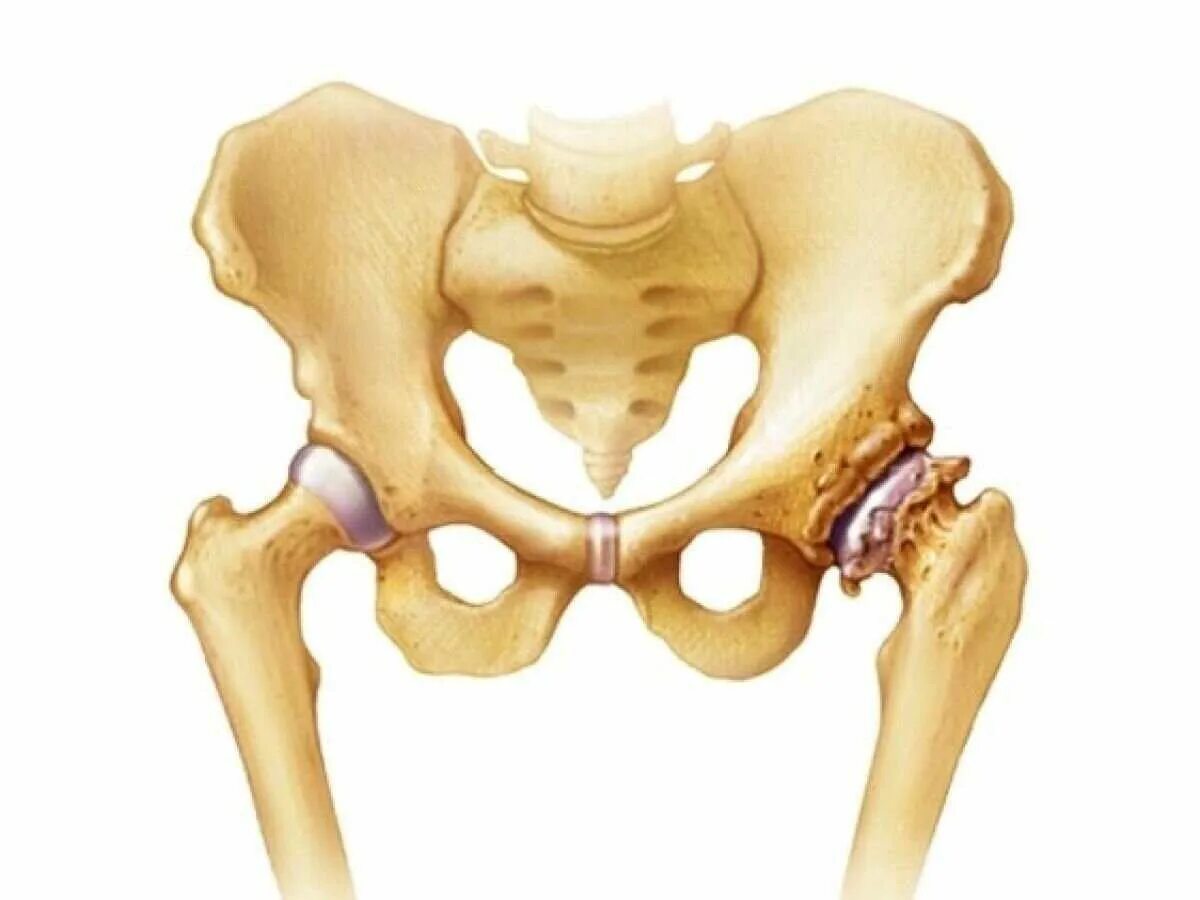

Тазобедренный сустав 3 степени лечение